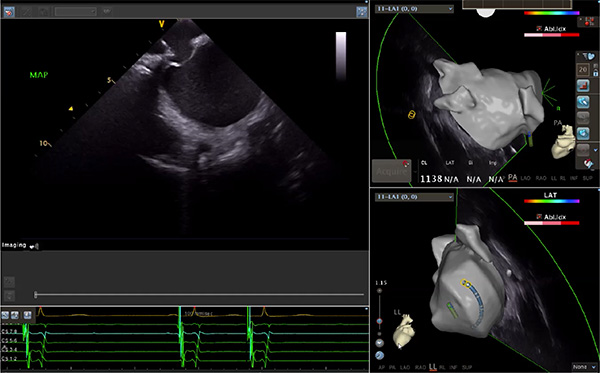

超聲心動(dòng)圖技術(shù)包括常規(guī)經(jīng)胸超聲(TTE)、經(jīng)食管超聲(TEE)、心腔內(nèi)超聲(ICE)、超聲聲學(xué)造影(MCE)、三維超聲心動(dòng)圖等,ICE是一種新興技術(shù)——將微型的換能器安裝在心導(dǎo)管的尖端,經(jīng)由外周血管輸送至心腔內(nèi)部,換能器發(fā)射聲波,對(duì)心臟及其鄰近組織進(jìn)行實(shí)時(shí)高質(zhì)量成像和(或)血流動(dòng)力學(xué)測(cè)定的超聲成像技術(shù)?;诓煌募夹g(shù)原理,心腔內(nèi)超聲導(dǎo)管被分為兩類:機(jī)械旋轉(zhuǎn)式超聲導(dǎo)管和相控陣超聲導(dǎo)管。目前,臨床上主要應(yīng)用的是相控陣超聲導(dǎo)管,ICE成像通過術(shù)者旋轉(zhuǎn)導(dǎo)管及操縱導(dǎo)管手柄上的兩個(gè)旋鈕來完成。

ICE門檻高、集成了超聲和圖像處理最前端的技術(shù),是當(dāng)前內(nèi)窺超聲方向最挑戰(zhàn)的領(lǐng)域。不同于傳統(tǒng)接觸式三維重建方法會(huì)產(chǎn)生假腔,影響術(shù)者對(duì)靶點(diǎn)或結(jié)構(gòu)的判斷,心腔內(nèi)超聲(ICE)可直接顯示心臟結(jié)構(gòu),有助于理解心臟內(nèi)各部位之間的解剖關(guān)系,不僅具有實(shí)時(shí)成像、并發(fā)癥監(jiān)測(cè)以及良好的耐受性,同時(shí)以股靜脈入路,無需全麻或深度鎮(zhèn)靜,日益成為心臟介入手術(shù)中重要輔助工具,被譽(yù)為心臟介入醫(yī)生的“黃金眼”。心腔內(nèi)超聲可用于多種心臟介入手術(shù),潛在患者群體龐大,動(dòng)脈網(wǎng)測(cè)算我國心腔內(nèi)超聲導(dǎo)管市場(chǎng)空間或?qū)⒊?00億元,具有廣闊前景。

隨著心腔內(nèi)超聲的應(yīng)用更廣,性能也在逐漸優(yōu)化,已從二維成像轉(zhuǎn)變?yōu)?strong>三維成像,極大增強(qiáng)了引導(dǎo)及可視化能力。二維心腔內(nèi)超聲支持雙平面或三平面成像,可顯示兩個(gè)或三個(gè)不同的平面視圖,但醫(yī)生需將這些圖像在腦海中重新構(gòu)建為三維解剖結(jié)構(gòu)。三維心腔內(nèi)超聲則可直接呈現(xiàn)三維解剖結(jié)構(gòu)圖,便于醫(yī)生更輕松地開展手術(shù)。按照產(chǎn)品發(fā)展方向,預(yù)計(jì)心腔內(nèi)超聲還將向更清晰、精準(zhǔn)、多功能等方向發(fā)展。